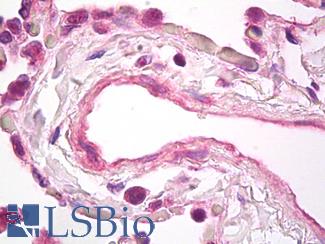

Smooth Muscle Actin (SMA / ACTA2)

Anti-Smooth Muscle Actin antibody IHC of human prostate, smooth muscle. Immunohistochemistry of formalin-fixed, paraffin-embedded tissue after heat-induced antigen retrieval. Antibody LS-B7351 dilution 1:50.